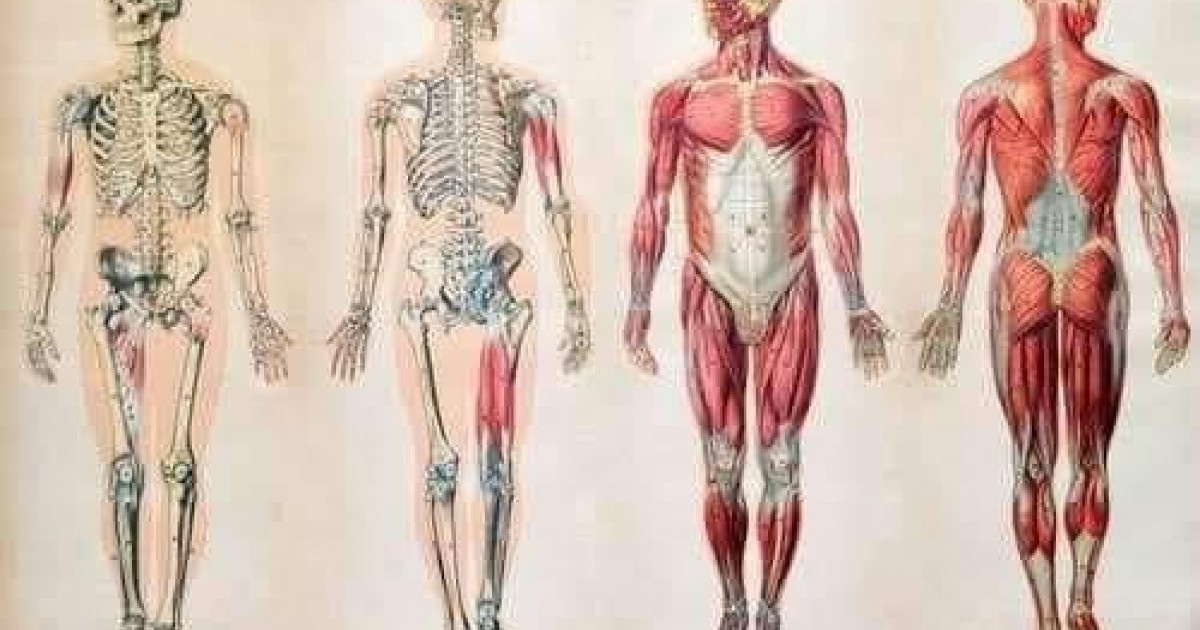

7 metara tankog crijeva![]() 230 komada kostiju

230 komada kostiju